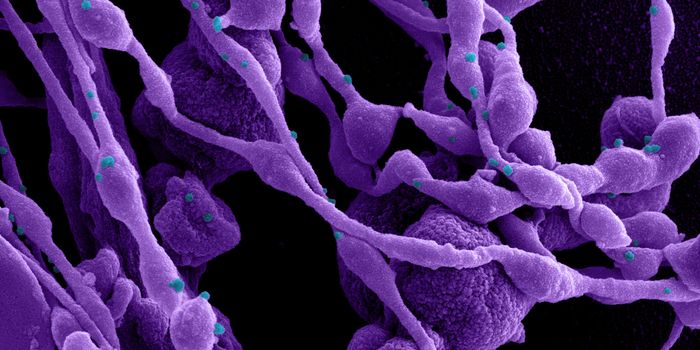

APR 04, 2022Cell & Molecular BiologyAbout 1.5 million new HIV infections are thought to have occurred last year, and while COVID-19 has dominated concerns a ...

FEB 21, 2022Cell & Molecular BiologyTwo people have been cured of HIV, and now, a US woman joins them. In this third case, stem cell transplants were being ...

NOV 30, 2021ImmunologyHIV is a master of disguise. Once the virus enters the body, it has a number of sophisticated mechanisms through which i ...

NOV 22, 2021MicrobiologyThough treatments are available, there is no cure or vaccine from HIV, which impacts about 38 million people worldwide. ...

SEP 06, 2021MicrobiologyHIV vaccines have remained elusive in part because the virus has a powerful ability to mutate, and there are so many str ...

JUN 24, 2021ImmunologyA new study has revealed how stem cells can be used to amplify immune responses to HIV, the virus that causes AIDS. The ...